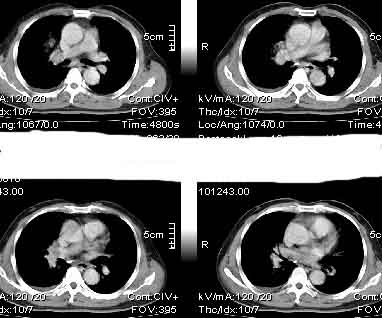

该病例我的诊断意见:右肺上叶周围型肺癌伴纵隔和右肺门淋巴结增大和右肺上叶阻塞性肺炎{病灶周围致密影以近肺门侧明显!}。右侧少量胸腔积液。

一. 1)症状有无发热及慢性过程.2)化验室检查?3)有无tb接触史?二.右肺上叶见片团状影,边界欠清,外侧方见一结节状软组织影,密度欠均匀,内可见低密度坏死区.周围强化明显,肺内见纤维索条影,局部胸膜增厚,但无明确胸膜凹陷.上叶支气管壁增厚,肺门及纵隔淋巴结增大.右侧胸腔少量积液.诊断意见:1右肺上叶慢性感染性疾病(肺tb?)伴肺门,纵隔淋巴结大.右胸少量积液.右肺上叶结节影多为tb球?2右肺上叶周围型肺ca伴肺门,纵隔淋巴结转移待排.右肺上叶炎变(肺门及纵隔淋巴结压迫).右胸少量积液.等待随返结果.

右上肺周围性肺癌,阻塞性肺炎考虑为肿大淋巴结压迫上叶支气管引起。